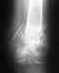

Именно этим я сегодня и занимался , Был на приёме у зав. отделением травмотологии ( именно там где делают операции ) Дело в том что гипс вообще был не нужен достаточно было пару недель походить с палочкой, кость именно от этого и не срастается что на неё не даётся нагрузка и кровь застаивается Мне объяснили что даже когда ломают и большую и малую кость в основном лечат только большую а на малую и внимания не обращают , мне сказали что бы я оставил кастыли и ходил без них в крайнем случае с палкой.